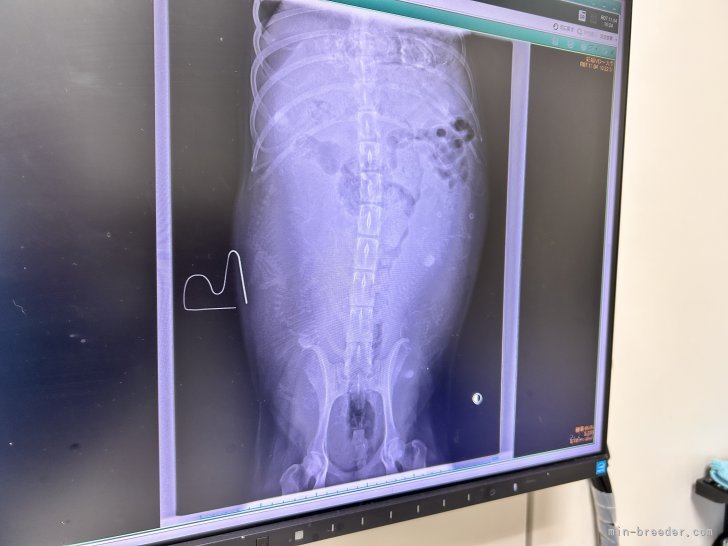

頭と背骨で何頭⁉️お腹にいるか確認しました。

確認できた数は8️⃣頭。赤ちゃんたちの混み具合から隠れて写っていない子がいると思われます。

私の予想ですが‥。